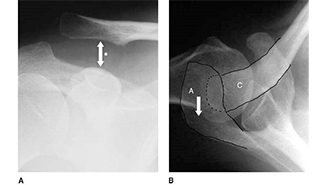

Diagnosis Spotlight shines a light on musculoskeletal injuries and conditions that are commonly missed on radiologic imaging. In these courses, you will review the factors contributing to diagnostic errors, and the essential pearls, pitfalls, and best practices for reducing misdiagnosis. Learn evidence-based strategies to avoid diagnostic errors, potentially reducing delay in treatment, reducing risk of malpractice claims, and improving outcomes for patients.